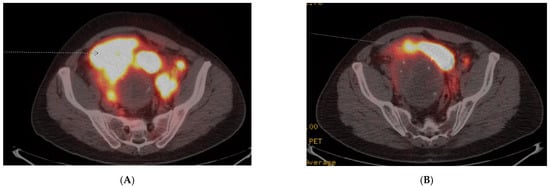

4. Case 3

A 45-year-old previously healthy male presented with episodic fevers and lower back pain, along with 10 kg intentional weight loss. Initial CT scan showed a large pelvic mass with retroperitoneal adenopathy and ipsilateral ureteric compression. Biopsy of the pelvic mass demonstrated a paraganglioma, with a Ki-67 of 30–40%. Given the rapid progression of disease, he received six cycles of carboplatin and etoposide first-line for six cycles. His pelvic pain, fevers and night sweats improved after the third cycle but recurred within one month of discontinuing chemotherapy. A Gallium-68 PET-CT was performed to determine eligibility for PRRT and documented heterogeneous uptake of a large dominant pelvic mass and extensive retroperitoneal adenopathy, Krenning score 4 (Figure 2A). The remainder of his imaging revealed extensive new onset right sided hydronephrosis and left supraclavicular adenopathy. The patient initiated second-line therapy with PRRT, prior to which he was started on prazosin 2 mg twice daily and atenolol 25 mg once daily. Symptoms significantly improved by the second cycle of PRRT and a total of four planned treatments of Lutetium-177 Dotatate, 7.4 GBq (200 mCi), were given without adverse reaction. A radiographic partial response to therapy was documented on follow-up Gallium-68 Dotate PET-CT (Figure 2B) and he discontinued both alpha and beta-blocker therapy until 8 months after PRRT treatment began, when his symptoms recurred and he was diagnosed with progressive retroperitoneal metastasis.

Figure 2. Case 3, (A) Baseline Gallium-68 Dotatate PET-CT demonstrated a large pelvic mass with retroperitoneal adenopathy and ipsilateral ureteric compression; (B) Follow-up Gallium-68 Dotatate PET-CT after 3 cycles of Lu-177 Dotatate demonstrated significant reduction in pelvic mass and retroperitoneal adenopathy.